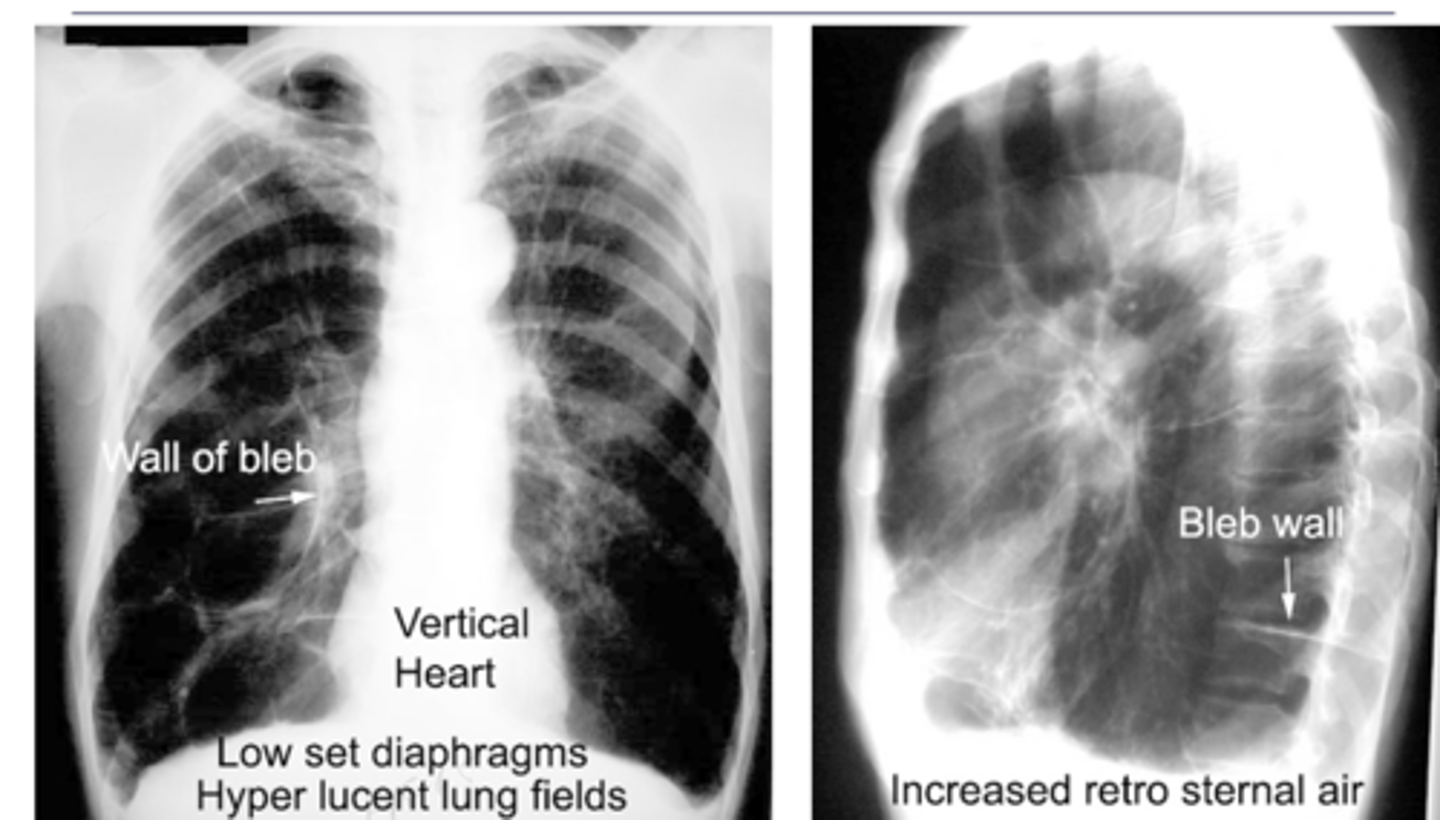

o Both terms refer to lung tissue with air space but no alveoli – (non-functioning).

o Bleb = less than 1 cm diameter

o Bullae = greater than 1 cm but often much larger

o Walls of lesion are very thin (often invisible)

o Difficult to see on CXR – can be seen as absence of pulmonary markings.

Often associated with COPD or emphysema but bullae can be present in normal asymptomatic patients. (this pt has emphysema)

-Flattening of hemidiaphragms with blunting of costophrenic angles.

-Increased AP diameter of chest on lateral view (barrel chest)

-Presence of bullae or large air cavities

Flattened diaphragms, ant mediastinal space increased --> COPD/emphysema

Dx and ID radiological findings